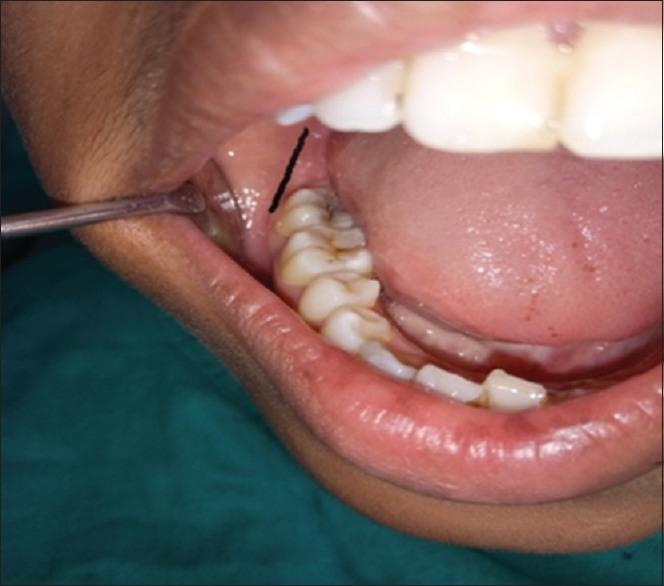

PAIN in the craniofacial and neck region can be both intriguing and equally frustrating for the surgeon. This is principally because there is a multitude of related pain syndromes in this region, many of which are lacking in physical signs. Diagnosis then becomes even more dependent on an accurate description of the pain in terms of character, localization, duration, radiation, relieving and exacerbating factors. Familiarity and identification of a more obscure causative factor in a particular case lends itself not only to liberate the patient but also an increased awareness of the practitioner for the need to consider the coinciding minute diagnostic points of otolaryngology, ophthalmology and rhinology besides dentistry and oral surgery. The characteristic elongation of a styloid process may explain some occasions of pharyngeal, ear pain and sometimes headache, which have defied exhaustive diagnostic studies. A large spectrum of signs and symptoms has been mentioned in various reports of Eagle's syndrome. Diagnosis can be made with careful clinical evaluation and confirmed with radiographs showing an elongated styloid process or calcification of the stylohyoid complex. Styloidectomy is the procedural choice for Eagle's syndrome having high success rate. In our case, the intraoral approach for styloidectomy was not the routine one, for which the post-operative outcome was exceptionally good without any complications.

颅面部和颈部区域的疼痛对于外科医生来说既引人关注又同样令人沮丧。这主要是因为该区域存在多种相关的疼痛综合征,其中许多缺乏体征。因此,诊断更加依赖于对疼痛的特征、定位、持续时间、放射部位、缓解和加重因素的准确描述。在特定病例中熟悉并识别出更隐匿的致病因素,不仅有助于使患者解脱病痛,还能提高从业者的认识,使其意识到除了牙科和口腔外科外,还需要考虑耳鼻喉科、眼科和鼻科的细微诊断要点。茎突的特征性延长可能解释了一些尽管经过详尽诊断研究仍无法明确病因的咽部、耳部疼痛,有时还有头痛的情况。在关于鹰综合征的各种报告中提到了广泛的体征和症状。通过仔细的临床评估可以做出诊断,并通过X线片显示茎突延长或茎突舌骨复合体钙化来确诊。茎突切除术是治疗鹰综合征的手术选择,成功率较高。在我们的病例中,茎突切除术采用的口内入路并非常规方法,术后效果非常好,没有任何并发症。